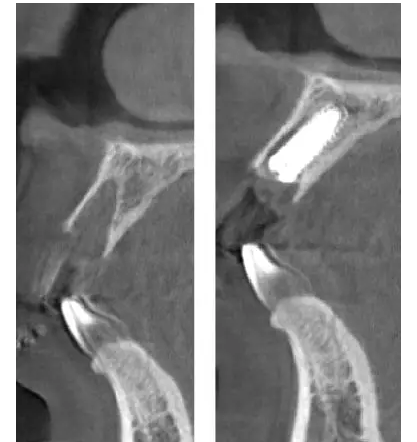

術(shù)前、術(shù)后CT

在口腔種植領(lǐng)域中,由于各種原因造成的種植牙局部牙槽突骨量不足或種植體周圍骨缺損的修復(fù)在種植外科的研究中已經(jīng)取得了重大突破。新一代的血漿提取物--濃縮生長因子(CGF,Concentrate Growth Factors)能夠明顯縮短術(shù)區(qū)成骨的時間,提高成骨質(zhì)量,促進(jìn)成骨及組織的愈合;具體有:引導(dǎo)骨再生技術(shù)、聯(lián)合骨膜表面覆蓋加速軟組織愈合、用于上頜竇提升、拔牙后即刻種植、牙槽嵴位點(diǎn)保存、頜骨囊腫的治療、牙槽骨修整。